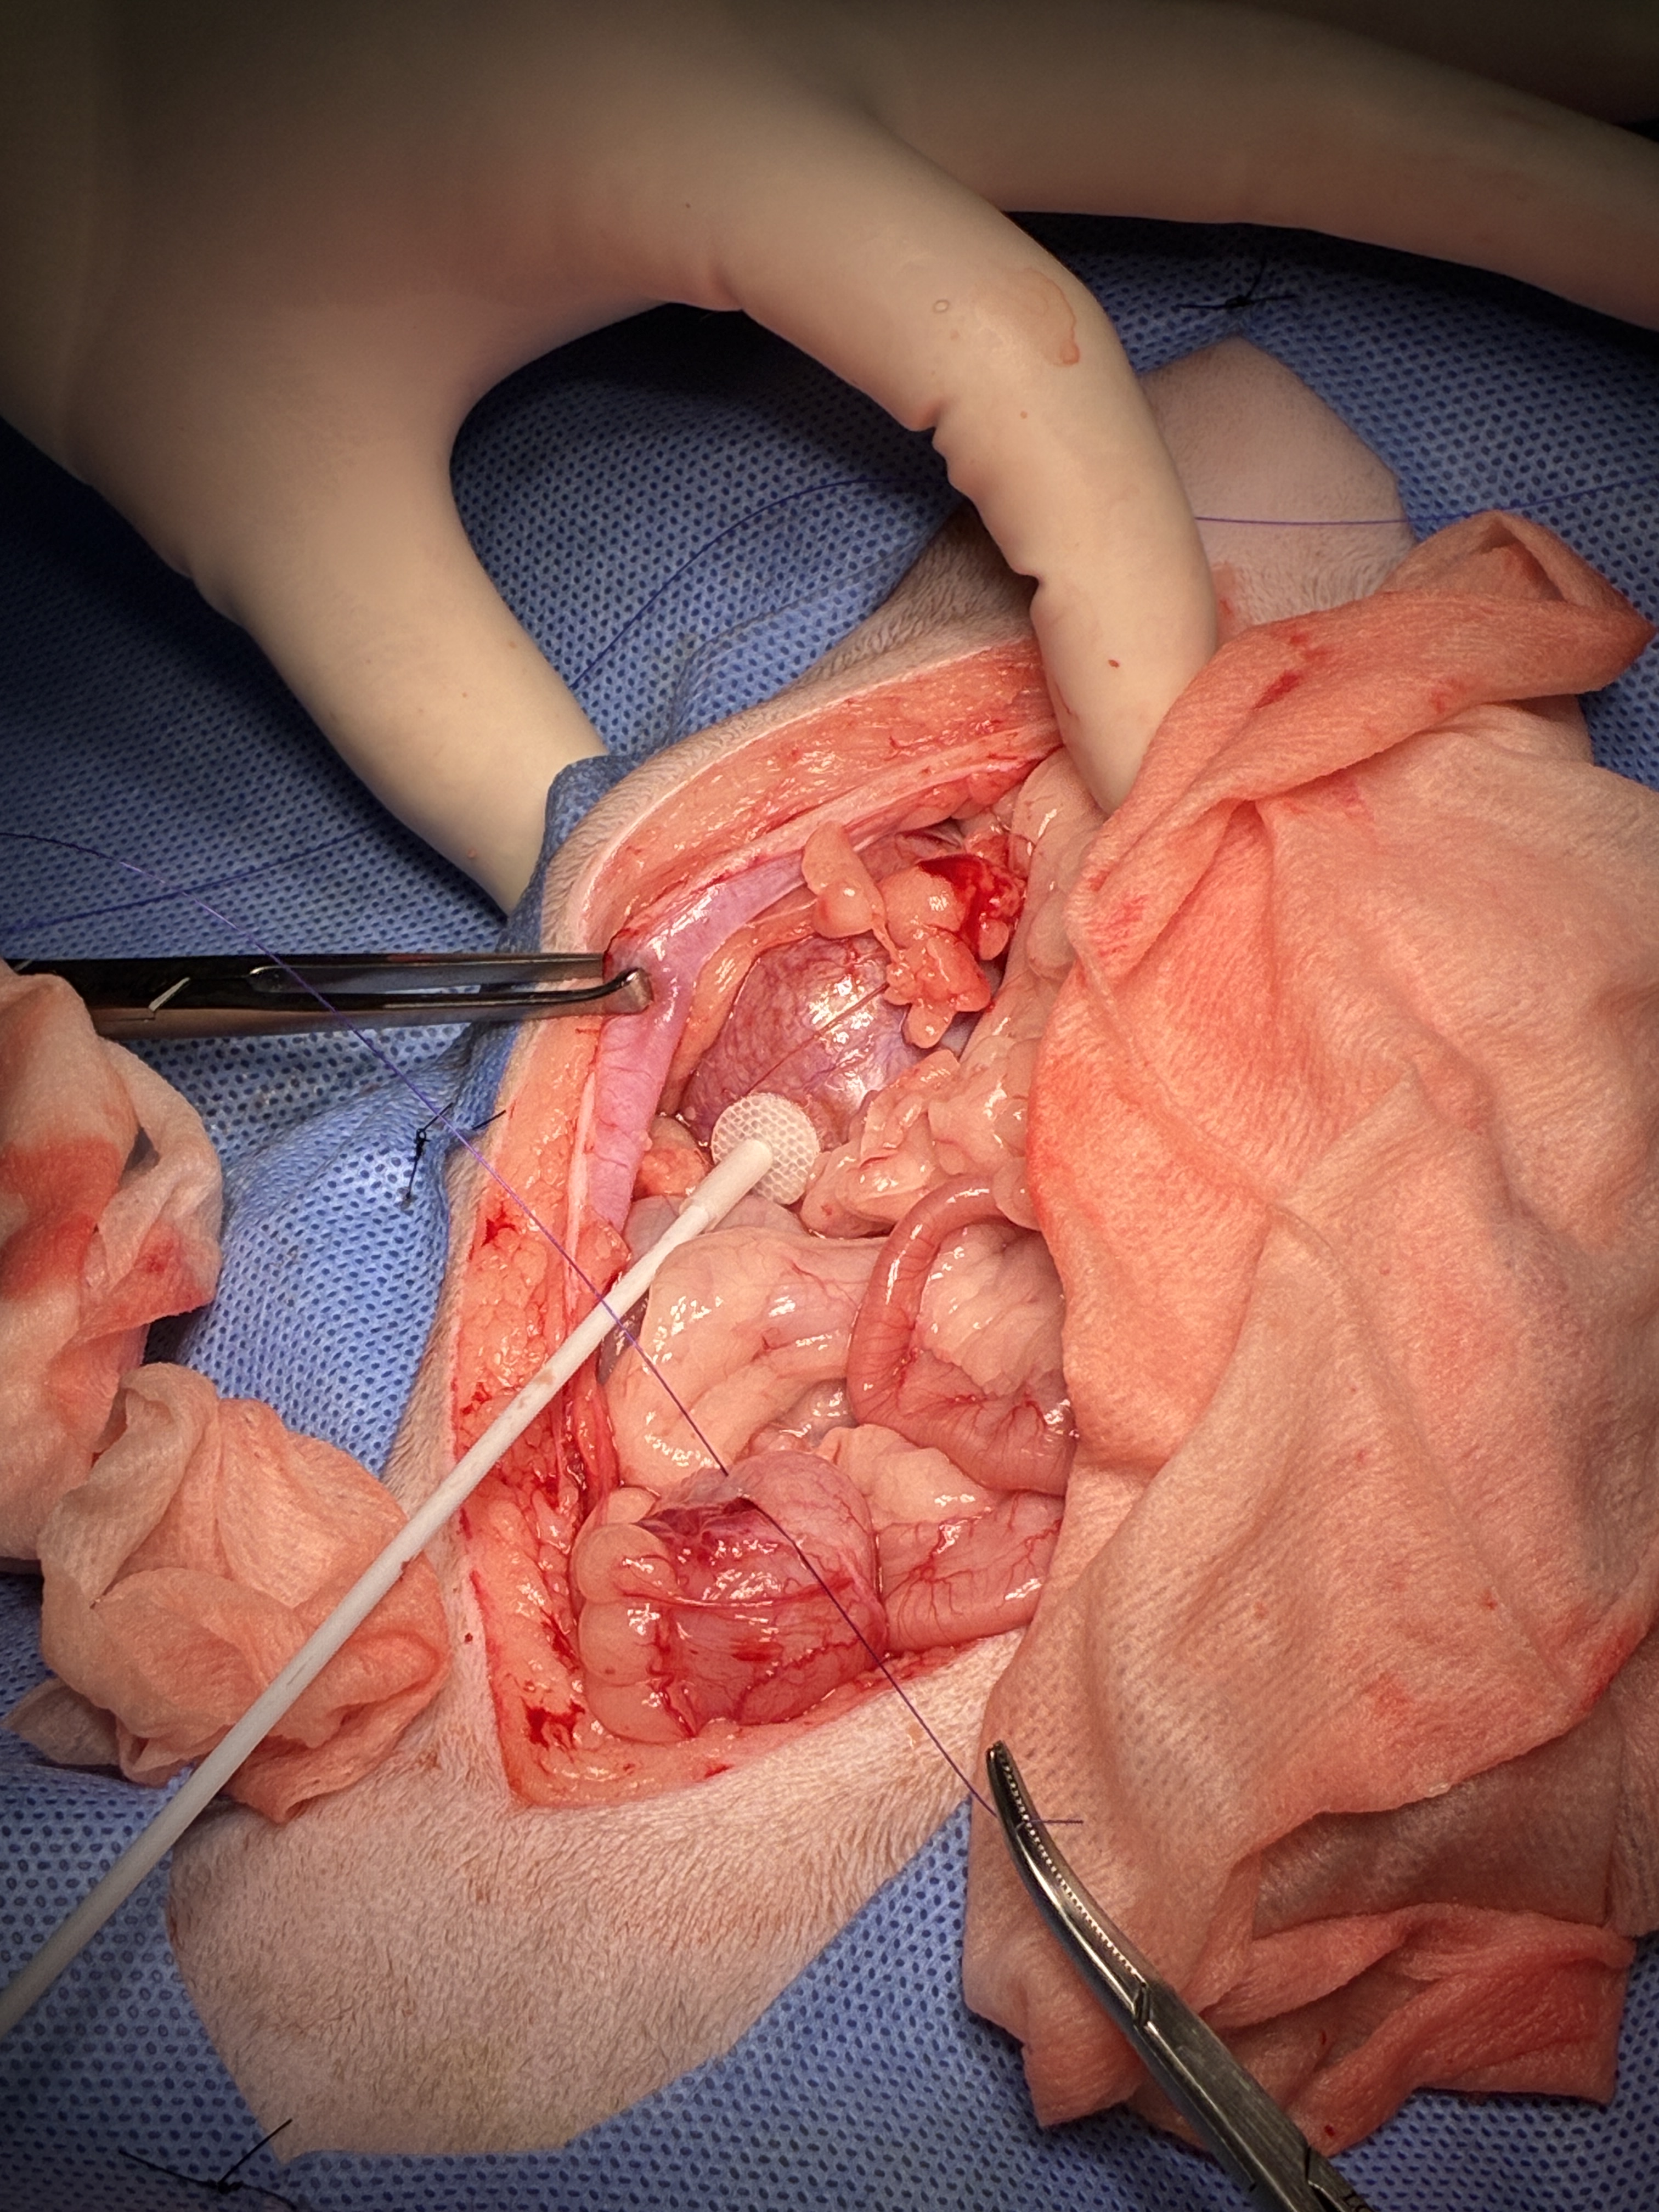

腹腔内のバイパス経路と膀胱です。

腹腔内のバイパス管接続部分です。